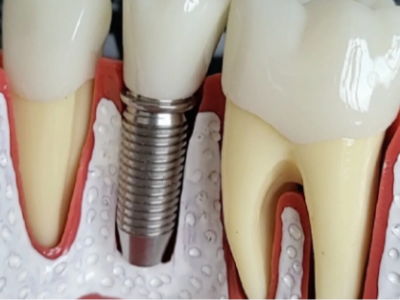

河北惟德口腔醫(yī)院告訴大家,針對(duì)不少缺牙患者,裝假牙尤其是半口、全口的在臨床上很常見(jiàn),很多人裝了假牙用不了多久就會(huì)出現(xiàn)各種問(wèn)題,嚴(yán)重的還需進(jìn)行更換,那2020承德?lián)Q半口牙大概多少錢(qián)呢?下面就給大家詳細(xì)介…